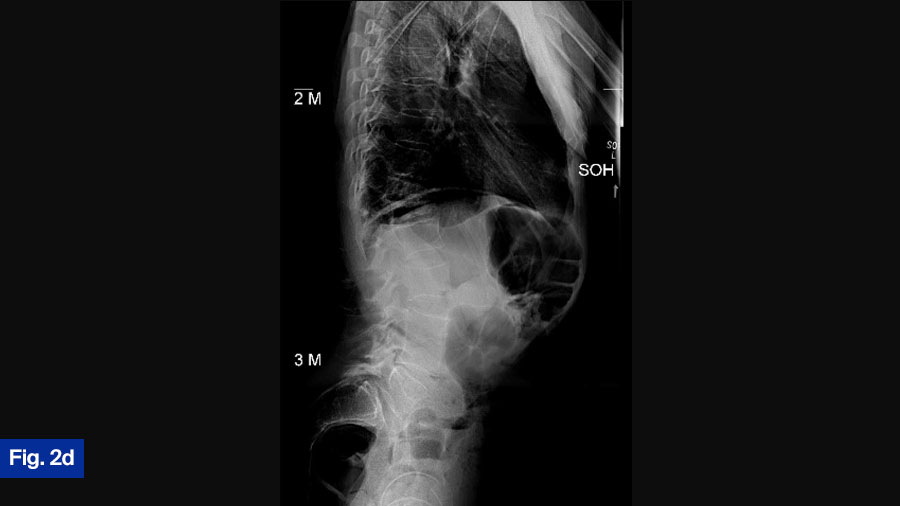

Actual treatment